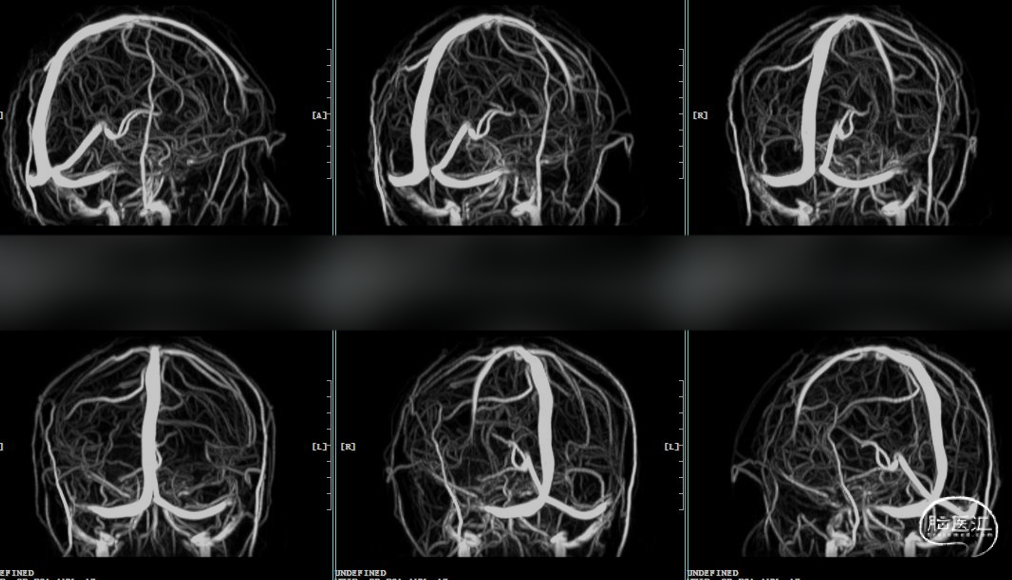

术前MRV:双侧横窦乙状窦交界重度狭窄。

术前DSA:双侧横窦乙状窦交界处重度狭窄。